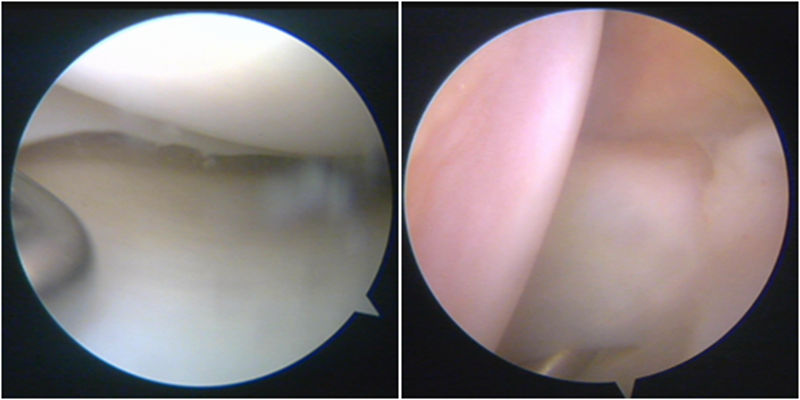

股骨侧保残骨道建立

股骨侧骨道建立,椭圆形扩孔保残9mm

韧带导入过程

送止血带后韧带表明血管膜